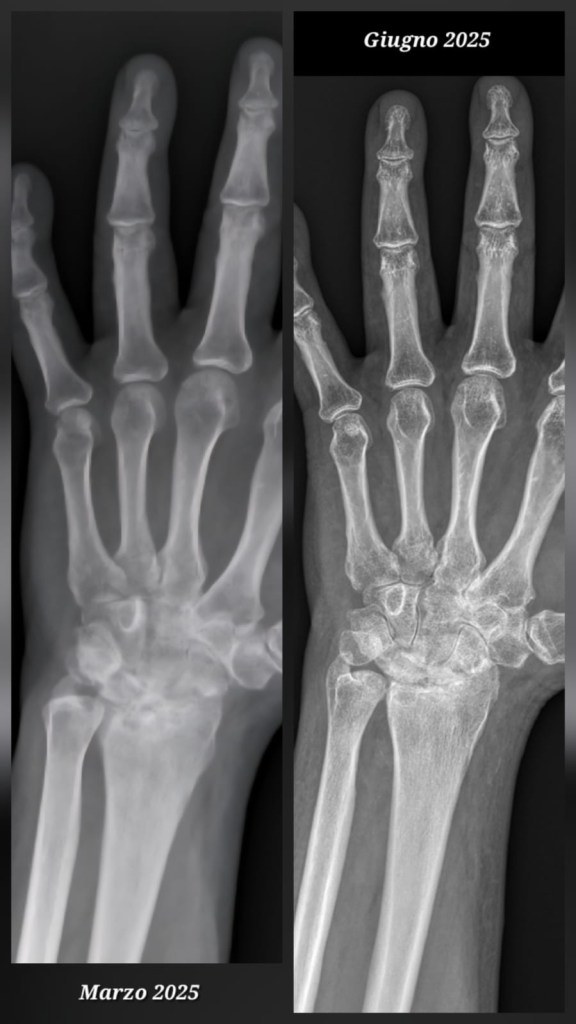

Dalla valutazione radiografica emerge una netta differenza rispetto all’esame di marzo, i segni tipici dell’artrosi risultano ridotti a giugno.